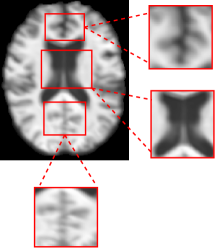

As a transitional state between NC and AD, MCI shows anatomical changes that may overlap with features of either class. This makes it particularly challenging for models to differentiate MCI from neighboring classes. Given an MCI sample, random affine transformations are applied in order to introduce slight translation, scaling and contrast adjustments so as to produce an augmented sample. These augmentations do not involve morphological changes, as such operations could risk rendering MCI samples more similar to either of its neighboring classes. Instead, they introduce moderate variations that increase diversity while keeping the anatomy realistic and helping the model generalize better to borderline cases. To further diversify MCI representations, if a batch consists of only MCI samples, sub-volume mixing is applied, where a random 3D volume is extracted from one sample and inserted at the same position in the other sample. This encourages the model to capture variations within each class while still keeping the classes separated (Fig. 5).

Refer to caption

(a)

(b)

(c)

Figure 5: CutMix pipeline: (a) Source image xax_{a}, (b) Source image xbx_{b}, (c) Region-wise patches are extracted and swapped to generate mixed image x~a\tilde{x}_{a} in 3D space.